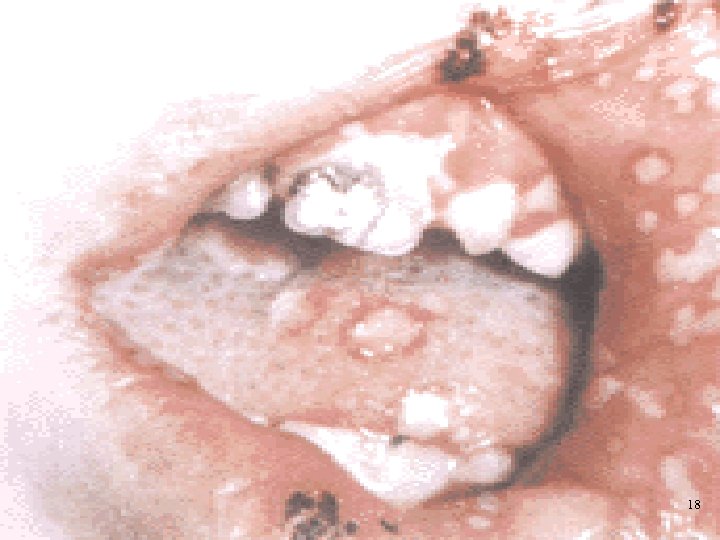

4. Инфекционные процессы, наблюдаемые у 80 -85% больных ОЛ, являются грозным, трудно купируемым осложнением Бактериальные инфекции-70 -80%: 4. пневмония 5. сепсис 6. гнойные процессы Тяжелые осложнения вирусного (4 -12%) и грибкового генеза (18 -20%). 17

18